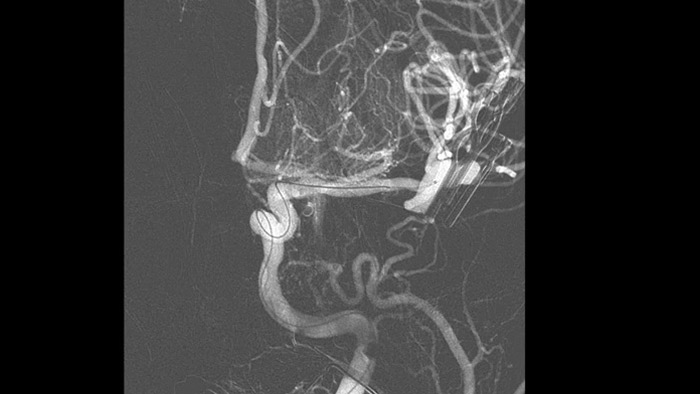

SmartCT Angio ist eine Röntgen-Erfassungstechnik, die eine vollständige, hochauflösende 3D-Darstellung der zerebralen Gefäße aus einem einzigen Rotationsangiographielauf erstellt. Sämtliche Funktionen werden dabei über den Touchscreen am Tisch gesteuert. Dies kann die Sichtbarkeit stark gewundener oder komplexer Anatomien verbessern, die auf einem 2D- oder DSA-Bild möglicherweise nicht zu sehen sind.

SmartCT Angio liefert in wenigen Sekunden eine volumetrische Darstellung und unterstützt so die Beurteilung von Position, Größe, Hals und Schweregrad des Aneurysmas für die Behandlungsplanung. Die 3D-Volumina werden mit hoher räumlicher Auflösung und automatischer Bewegungskompensation dargestellt.